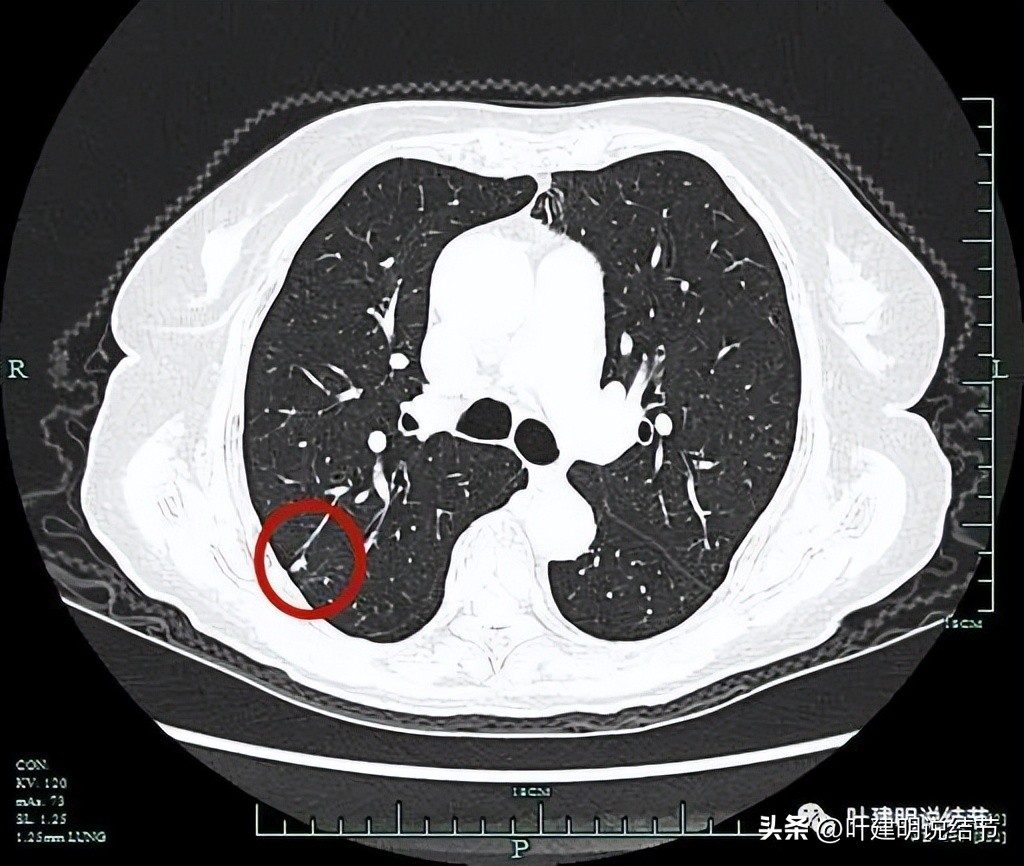

病灶出现,实性,有微小血管进入。